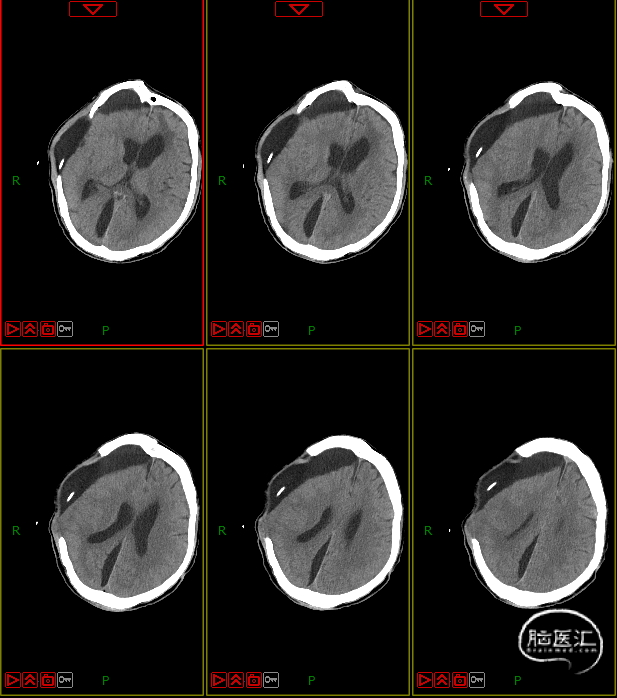

4. 动态复查头部CT

8月21日复查CT:硬膜下积液增加,脑室扩张明显,间质性水肿加重;对患者治疗方案进行调整,转神经外科治疗。